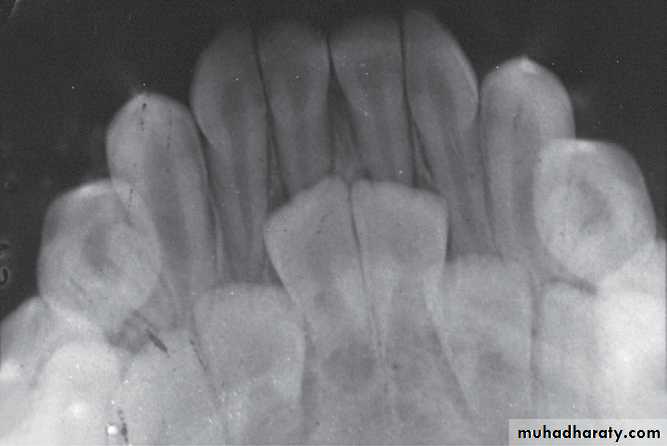

Occlusal RadiographIndications:

Determine the presence, shape and position of midline supernumerary teeth.Determine impaction of canines

Determine the presence or absence of incisors

Assess the extent of trauma to teeth and anterior

segments of the arches

Occlusal radiographSupernumerary tooth

Detection the Presence of permanent anterior teethOcclusal radiograph